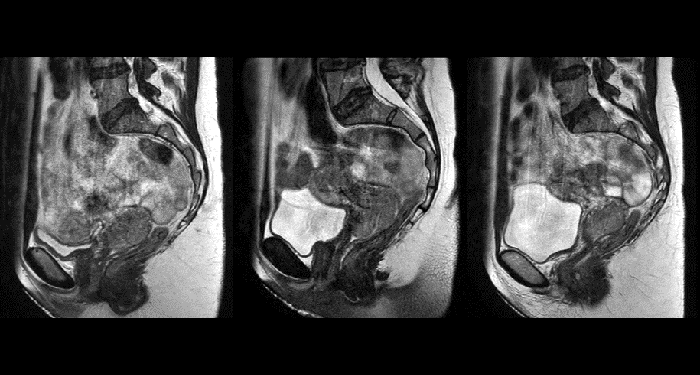

Grâce à ses capacités exceptionnelles de visualisation des tissus mous et à sa large gamme de contrastes des images, l’IRM est devenue un outil puissant qui permet de définir plus précisément les limites de la tumeur. Cette information est particulièrement importante, car il a été établi qu’il existe un degré élevé d’incertitude dans la délimitation du volume cible. Elle représente même la plus grande incertitude de l’ensemble du processus de radiothérapie pour la plupart des sites tumoraux**. Une meilleure visualisation de la zone cible et des organes à risque à proximité est un facteur clé pour améliorer la délimitation du volume cible. Le rôle croissant de l’IRM peut également être attribué à ses fonctionnalités d’imagerie, qui peuvent apporter des informations sur la caractérisation de la cible comme sur la réponse au traitement.

Grâce à un contraste des tissus mous supérieur à celui de la TDM, l’IRM offre une visualisation exceptionnelle des limites tumorales et de la proximité des structures critiques avoisinantes.

La possibilité de régler les contrastes peut fournir des informations encore plus précieuses sur les caractéristiques et l’étendue de la tumeur afin d’en faciliter la délimitation et offrir également des possibilités de stratégies d’augmentation de dose.